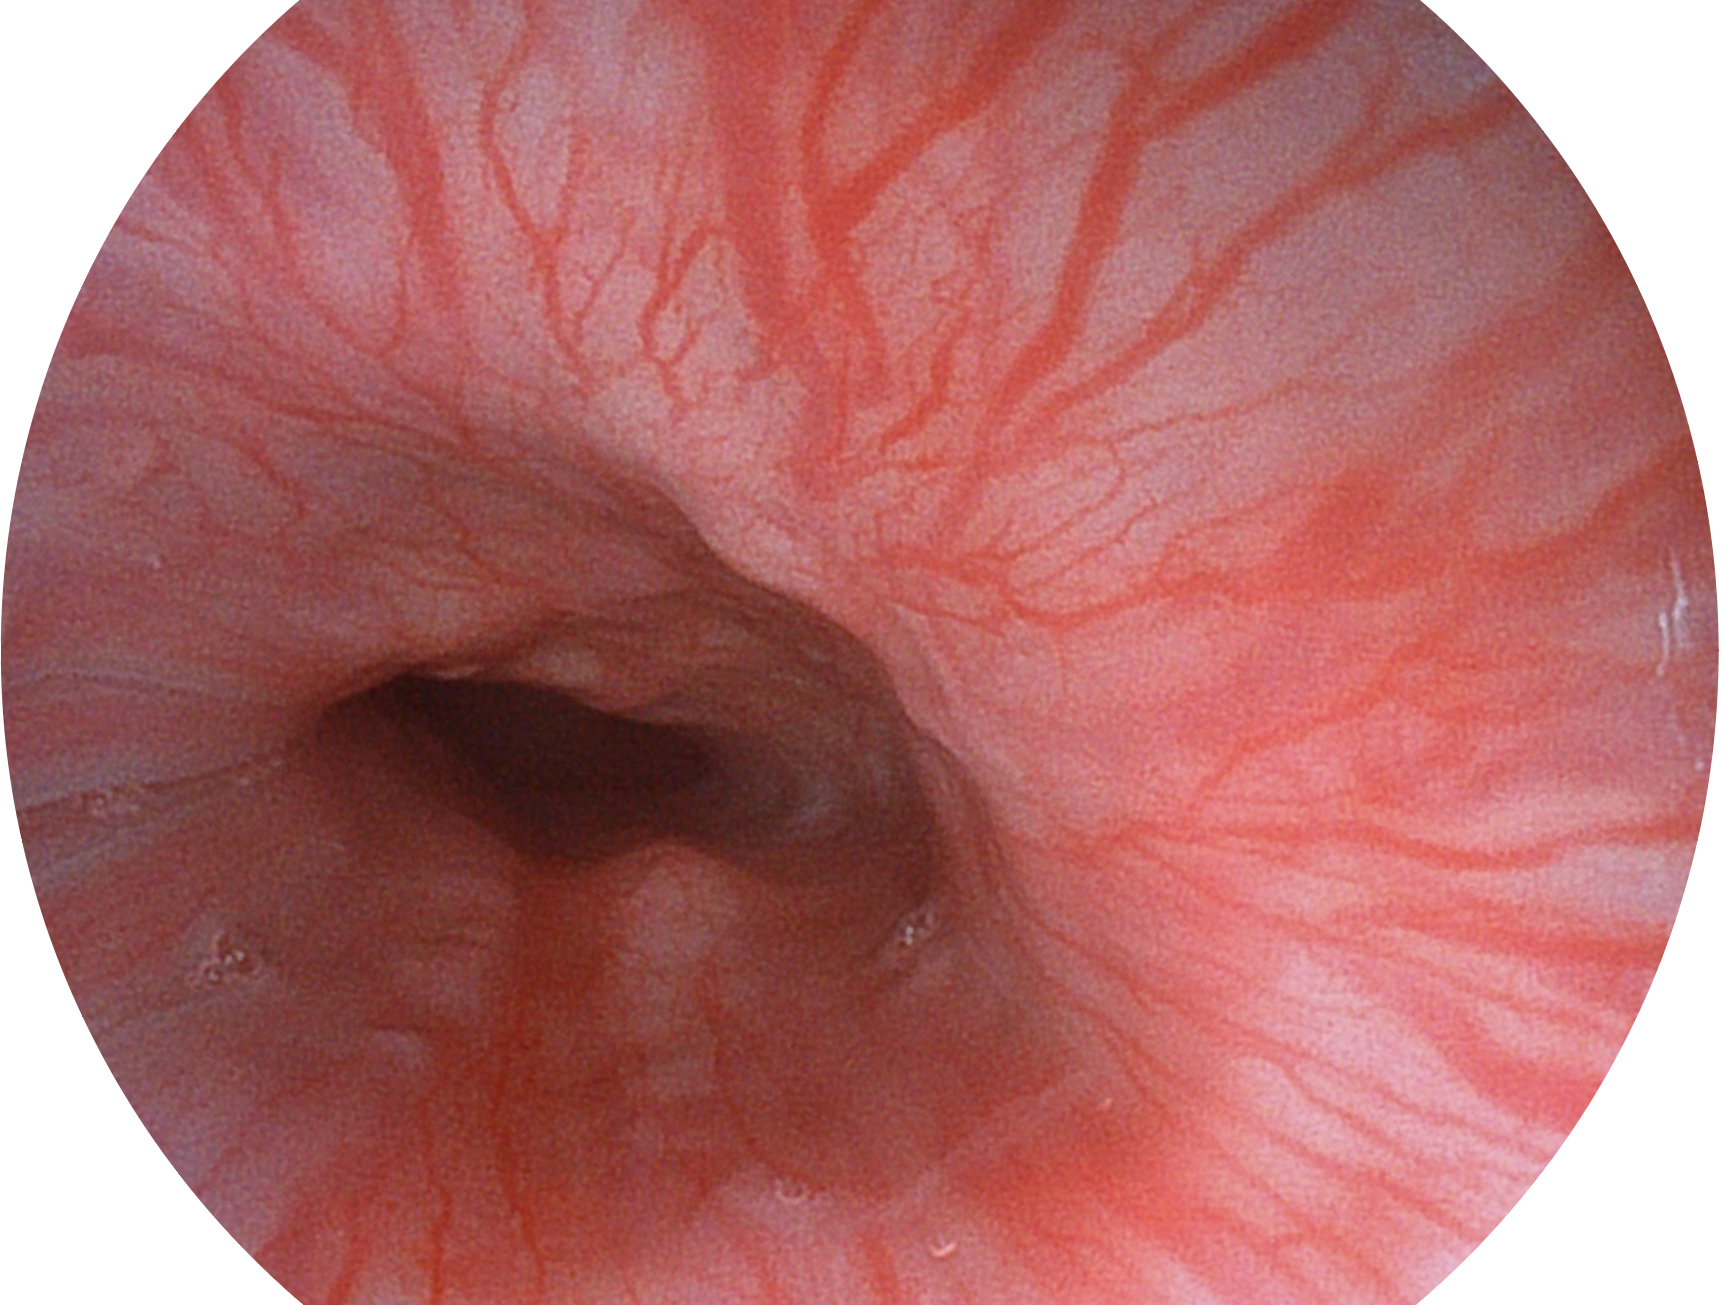

開立新開發(fā)的內(nèi)鏡染色技術(shù),主要是基于多波長(zhǎng)LED 光源的開發(fā),VLS-55Q 四波長(zhǎng)LED 光源是由四個(gè)不同顏色的LED光按照相應(yīng)照明模式所規(guī)定的特定發(fā)光比例進(jìn)行合束后形成,合束后形成的照明光的光譜由紅光、綠光、藍(lán)光及藍(lán)紫光這四個(gè)不同的波段范圍構(gòu)成。具有更高光譜自由度,通過光譜比例的控制,實(shí)現(xiàn)了聚譜成像技術(shù),英文全稱為“Spectral Focused Imaging, SFI”,縮寫為“SFI”和光電復(fù)合染色成像技術(shù),英文全稱為“Versatile Intelligent Staining Technology, VIST”,縮寫為“VIST”。